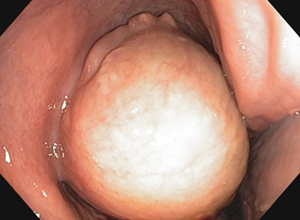

Sinuszysten sind gutartige, flüssigkeitsgefüllte „Blasen“, die erst stören, wenn sie verdrängend und raumfordernd wachsen. Sie können bei Pferden jeglichen Alters vorkommen und sollten operativ entfernt werden, wenn die oben genannten Symptome auftreten.

Andere Tumoren im Kopfbereich können von den Weichteilen, Knochen oder Zähnen ausgehen. In diesen Fällen ist eine umfangreiche Diagnostik notwendig, zu der auch eine endoskopische Untersuchung der Nasengänge und ggf. Nasennebenhöhlen gehört. Es gilt festzustellen, ob der Tumor gut- oder bösartig ist und wie weit und wohin er sich bereits ausgedehnt hat, um ihn im Anschluss chirurgisch zu entfernen. Bei Tumoren, die von den Weichteilen ausgehen, z. B. Polypen, kann eine Endoskopie-gestützte Entfernung mit einer Schlinge oder einem Laser erfolgreich sein. Dies sind äußerst elegante Methoden, die am stehenden Pferd ohne chirurgischen Zugang von außen erfolgreich sein können.